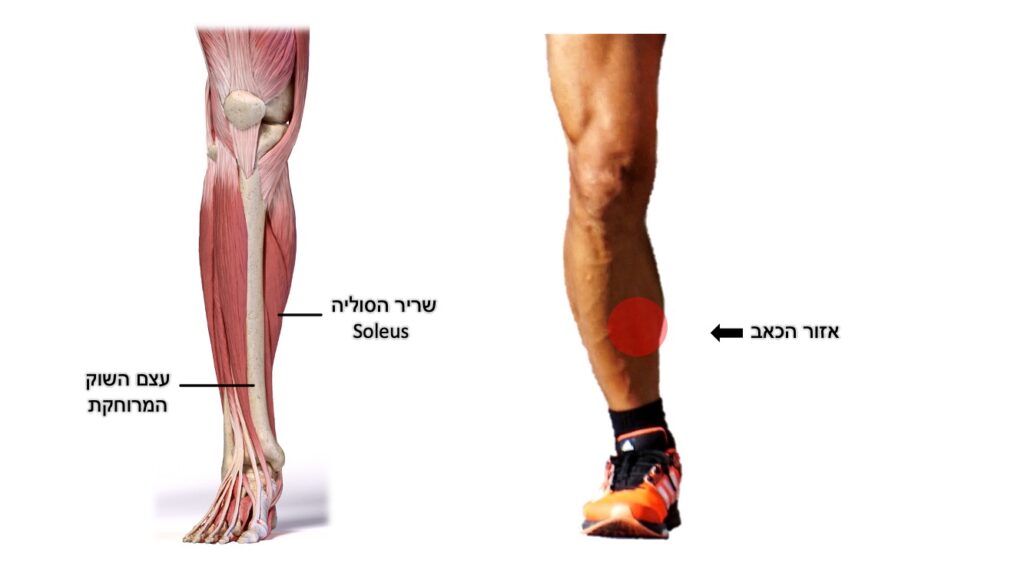

טנדינופתיה של גיד אכילס

Achilles tendinopathy

שריר התאומים ושריר הסולייה (soleus) מתחברים לעצם העקב באמצעות גיד אכילס ומייצרים תנועה של כיפוף כפי בקרסול (Plantar flexion). גיד אכילס הוא הגיד העבה בגוף האדם והוא מייצר וסופג כוחות משמעותיים בפעילות שגרה ובעיקר בפעילות גופנית.

פציעה זו שמערבת את הגיד היא פציעה שכיחה שגורמת לכאב ממוקם על פני הגיד, בחלק האחורי של הקרסול או מעליו, כתלות באזור המעורב של הגיד. הכאב יתחיל ככאב תלוי פעילות, אך לאחר מכן יכול להיות גם כאב לאחר פעילות ואף כאב במנוחה/הליכה רגילה. לעיתים תופיע נפיחות מקומית.

פציעה זו נובעת מכשל בתהליכי הריפוי המקומיים בתגובה לעומסים החוזרים על הגיד וסביבתו. מדובר בעיקר על תהליך שחיקתי (ניווני) בגיד שלעיתים מלווה גם בתהליכים דלקתיים. גורמים שהוזכרו בהקשר לפציעה זו כוללים: אספקת דם פחותה לאזור, חולשה שרירית, מבנה כף רגל עם קשה גבוהה, אי יציבות של הקרסול, שימוש בתרופות כדוגמת אנטיביוטיקה ממשפחת הפלורוקינולונים ועוד.

במסגרת תהליך האבחון יש לשלול סיבות אחרות לכאבים דומים כגון: תגובת מאמץ של העצם, תסמונת צביטה אחורית בקרסול, אי יציבות קרסול ועוד. על כן, חשוב לעבור הערכה רפואית מקצועית של מומחה בתחום.

הטיפול מבוסס על הימנעות ממאמצים המחמירים את הכאב ופיזיותרפיה שתתמקד בעבודה על גמישות (מתיחות) וחיזוק (אקסצנטרי) של שרירי השוק וכף הרגל בדגש על שרירי התאומים והסוליה. טיפול נוגד דלקת יכול לסייע במצבים החריפים. בהעדר מידע מוכח ניתן לשקול גם טיפולים בגלי הלם, מדרסים או כרית הגבהה לעקב, טיפול מקומי מסוגים שונים ועוד. חשוב מאוד להיות סבלניים ולנהל עומסים בצורה נכונה עד חזרה לפעילות מלאה ולעיתים ידרשו שבועות ארוכים עד חודשים של שיקום.

במקרים עקשניים ניתן לשקול טיפול בהזרקות. הזרקה של חומרים סטרואידים לא מומלצת לגיד זה בשל הסכנה לפגיעה בגיד לאחר ההזרקה, עד כדי קרע שלו. הזרקה של חומרים ביולוגים כדוגמת פלסמה עשירת טסיות (PRP) היא בטוחה יותר ונחשבת טיפול אפשרי בשילוב עם פיזיותרפיה ותרגילים, אם כי לא קיימות הוכחות מובהקות על עליונות טיפול זה על טיפולים אחרים.

במקרים בהם הטיפולים הלא-ניתוחיים כשלו, ישקל טיפול ניתוחי המותאם לאזור הפגוע בגיד.